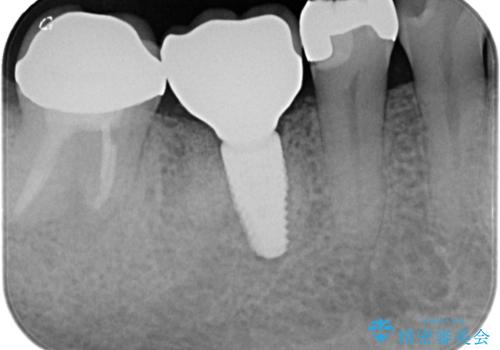

骨が成熟するまで待ち、インプラントを埋入しました。

被せ物はオールセラミッククラウンを被せています。

- 550,000円(インプラント代220,000円+カスタムアバットメント110,000円+オールセラミッククラウン110,000円+骨造成110,000円)費用は治療当時の料金となります